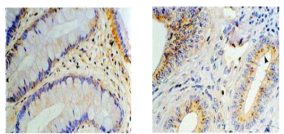

4)組織、細胞標本的免疫組化檢測;